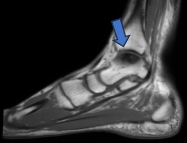

- Fracturas de Tobillo y Huesos del Pie: Fracturas complejas como las del calcáneo (hueso del talón) o los metatarsianos que demandan un abordaje preciso y especializado.

El impingement de tobillo es un pinzamiento de tejidos en la articulación, frecuente en deportistas. Causa dolor y limitación del movimiento, especialmente al flexionar o extender el tobillo.

- Cirugía: Artroscopia (elimina el tejido que causa el pinzamiento).